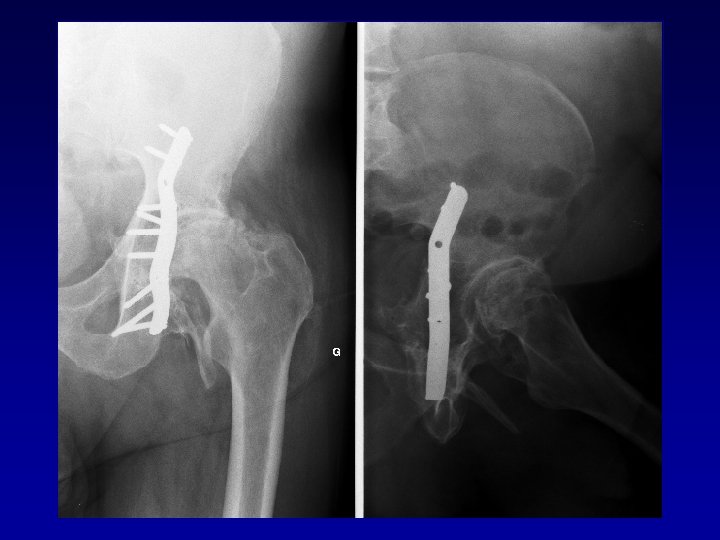

Bilan • • Type de fracture du cotyle Déformation de la cavité cotyloïdienne Chirurgie préalable Raideur Ostéome Nécrose de la tête fémorale Luxation invétérée

Déformation du cotyle • Ascensionné • Perte de substance osseuse scanner • Pseudarthrose • Perte du positionnement exact (idem LCH) • Doit être reconstruit et recentré

Chirurgie préalable Le matériel en place • Gêne le creusement, la reconstruction Les complications

Chirurgie préalable Le matériel en place • Gêne le creusement, la reconstruction Les complications • Nerveuses : sciatique, crural, fessiers (EMG) • Infectieuses

Arthroplastie totale de hanche sur fracture du cotyle complexe Recentrage, reconstruction, orientation du cotyle • • Greffe Ostéosynthèse par plaque MK Surtout si pseudarthrose Réduction de la luxation